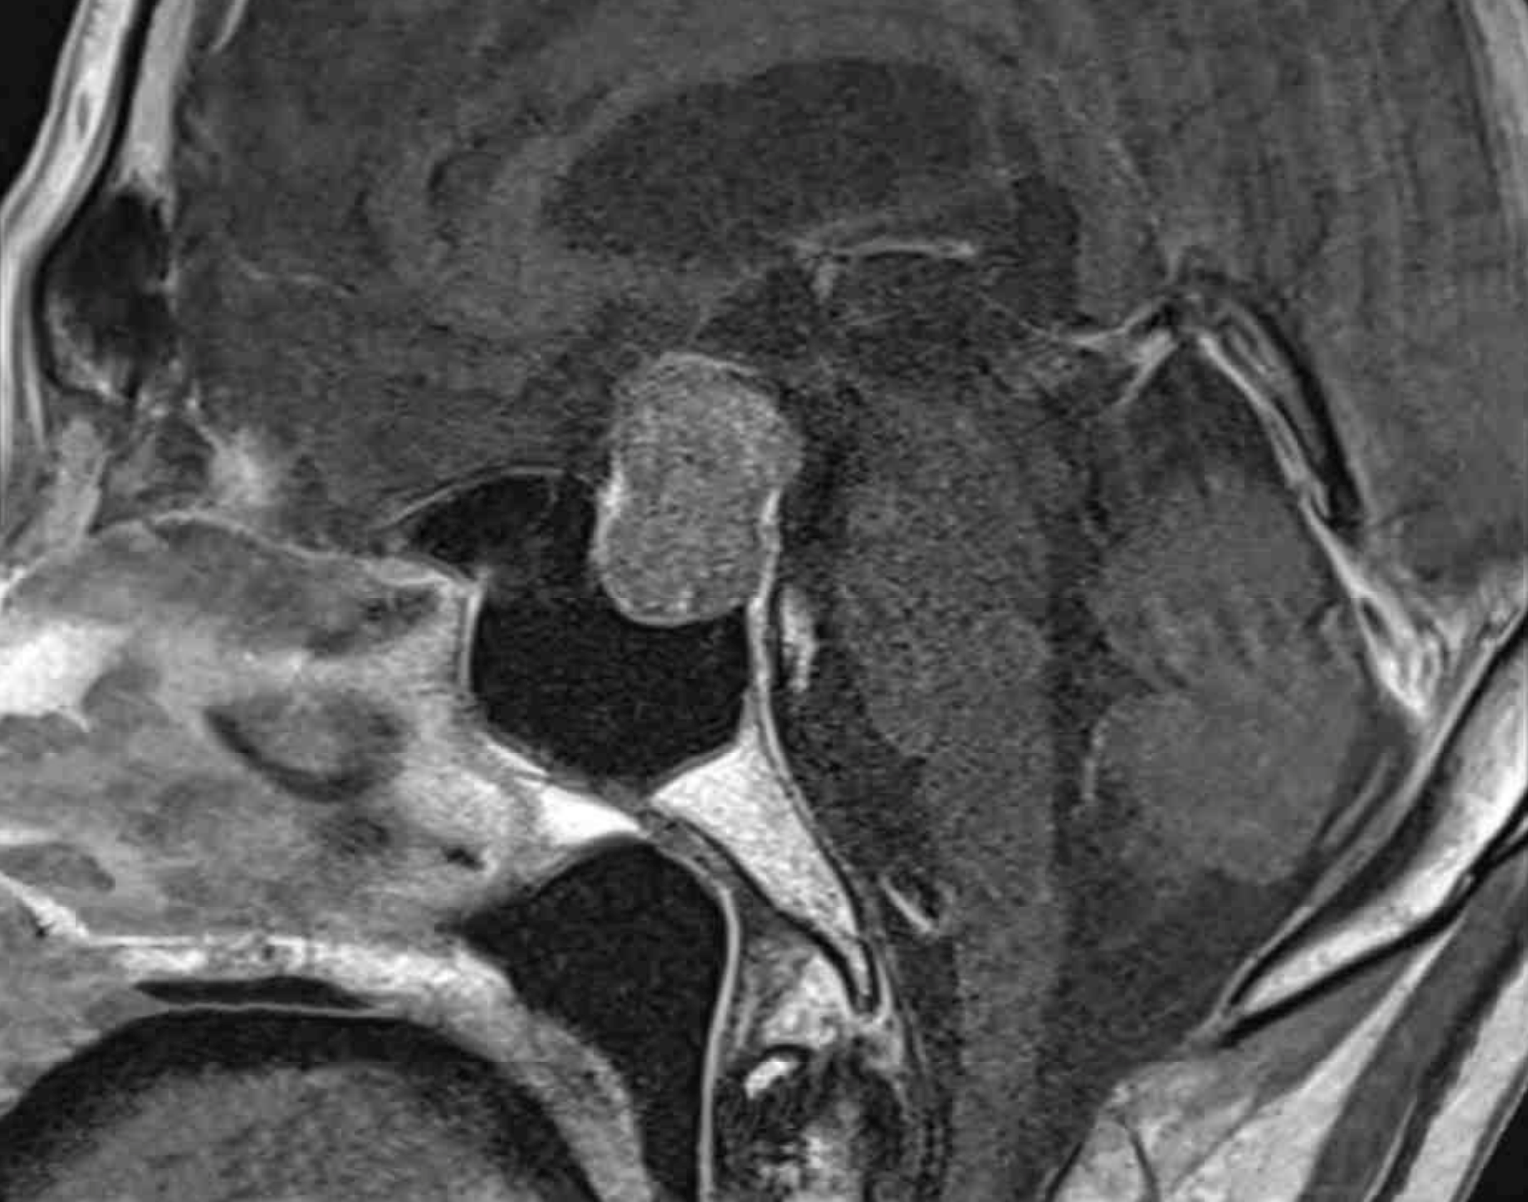

54세 남자가 1주 전부터 입맛이 없고 피곤하다며 병원에 왔다. 기저질환과 복용 중인 약물은 없다. 키 178cm, 몸무게 60kg, 혈압 80/50 mmHg, 맥박 98회/분, 호흡 20회/분, 체온 36.3℃이다. 액모와 음모가 보이지 않는다. 검사 결과는 다음과 같다. 안장 자기공명영상 사진이다. 치료는?

Sella MRI: Pituitary mass

Imp: 뇌하수체 기능저하증(hypopituitarism), 비기능성뇌하수체종양(nonfunctioning pituitary adenoma, NFPA)

여러 호르몬 결핍에 의한 증상과 검사소견을 보이고 sella MRI상 pituitary adenoma 확인되므로 NFPA에 의한 panhypopituitarism 진단하, 부족한 호르몬을 순서대로 보충하기 위해 glucocorticoid부터 투여한다.

• Sella MRI에서 pituitary adenoma가 확인되므로 종양 때문에 hypopituitarism이 발생했음을 알 수 있다.